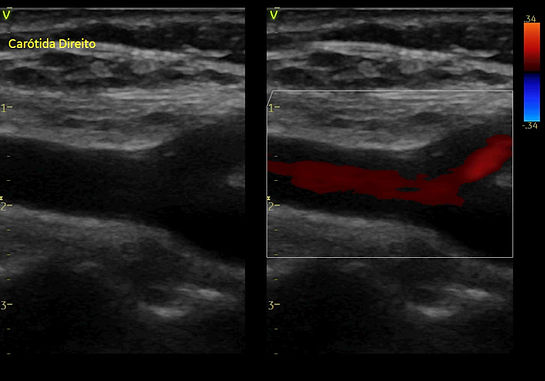

Ultrassom de Carótidas

O ultrassom de carótidas, também conhecido como ecodoppler de carótidas, é um exame de imagem não invasivo utilizado para avaliar o fluxo sanguíneo nas artérias carótidas, localizadas no pescoço. Essas artérias são responsáveis por fornecer sangue ao cérebro. O exame é essencial para detectar estreitamentos (estenoses), obstruções ou outras anomalias nas carótidas que possam aumentar o risco de acidente vascular cerebral (AVC).

Uso do Transdutor: O técnico de ultrassom ou radiologista utiliza um dispositivo chamado transdutor, que é colocado sobre a pele do pescoço. O transdutor emite ondas de ultrassom que penetram nas artérias e retornam ao dispositivo após refletirem nas paredes das artérias e no sangue em movimento.

Aquisição das Imagens: As ondas de ultrassom refletidas são convertidas em imagens que mostram as artérias carótidas e o fluxo sanguíneo dentro delas. A técnica Doppler é usada para medir a velocidade do fluxo sanguíneo e identificar áreas de fluxo turbulento que podem indicar estreitamentos ou obstruções.

Análise dos Resultados: As imagens e os dados coletados são analisados pelo médico, que verifica a presença de:

Placas de ateroma (depósitos de gordura) que podem estreitar as artérias

Estenoses (estreitamentos) significativas

Fluxo sanguíneo anormal que pode sugerir risco de AVC

Avaliação em Tempo Real: Permite observar o fluxo sanguíneo em tempo real, proporcionando uma avaliação dinâmica das artérias carótidas.